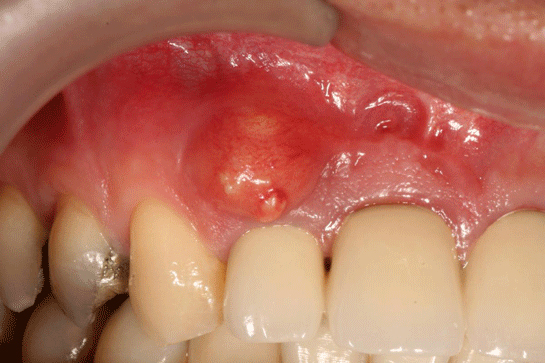

Diş iltihabı, dişlerin etrafındaki dokuların iltihaplanması durumunu ifade eder ve genellikle diş eti iltihabı (gingivitis) veya diş kökü iltihabı (apikal periodontitis) olarak sınıflandırılır. Diş iltihabının belirtileri ve tedavi yöntemleri, hastalığın evresine ve türüne göre değişiklik gösterir. Bu makalede diş iltihabının belirtileri, nedenleri ve tedavi yöntemleri üzerinde durulacaktır. Diş İltihabının Belirtileri Diş iltihabının belirtileri, genellikle aşağıdaki gibi sıralanabilir:

Ekstra Bilgiler Diş iltihabının tedavisinde erken müdahale oldukça önemlidir. İltihabın ilerlemesi durumunda, tedavi süreci zorlaşabilir ve daha ciddi sağlık sorunlarına yol açabilir. Ayrıca, diş iltihabının genel sağlığa etkileri de göz ardı edilmemelidir. Araştırmalar, diş eti hastalıklarının kalp hastalıkları, diyabet ve diğer sistemik hastalıklarla ilişkili olabileceğini göstermektedir. Bu nedenle, bireylerin ağız sağlığına dikkat etmeleri ve düzenli olarak diş hekimine gitmeleri büyük önem taşımaktadır. Sonuç olarak, diş iltihabı belirtilerinin erken tanınması ve uygun tedavi yöntemlerinin uygulanması, sağlıklı bir ağız yapısının korunmasına yardımcı olacaktır. Unutulmamalıdır ki, diş sağlığı sadece ağız sağlığı değil, genel sağlık için de kritik bir öneme sahiptir. |